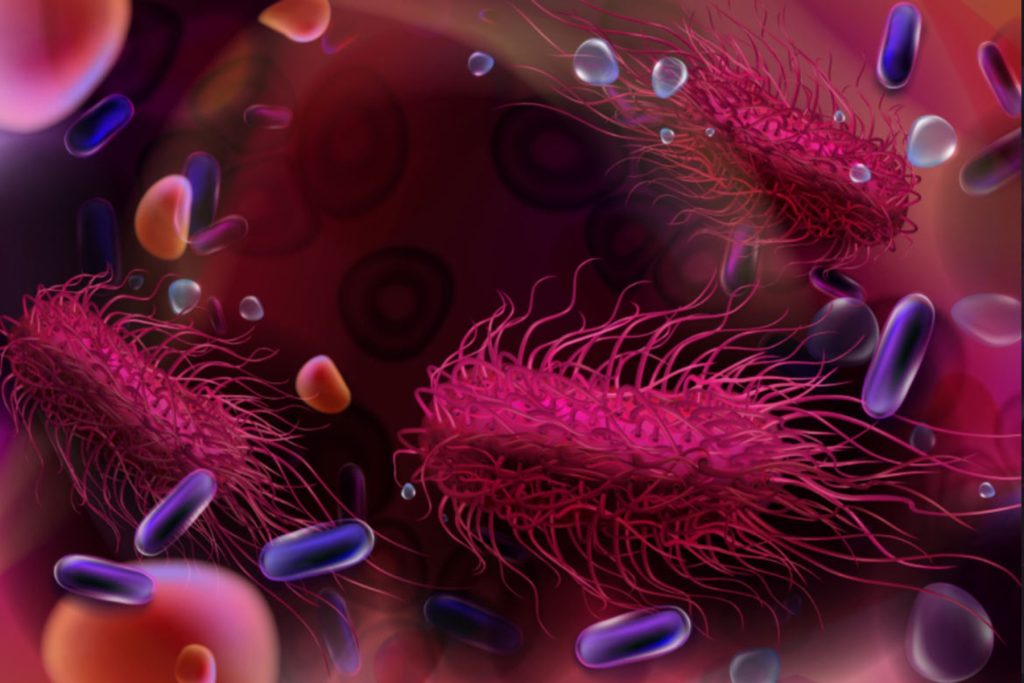

ΣΥΜΠΤΩΜΑΤΑ

Μαστοειδίτιδα: Τι είναι και πώς αντιμετωπίζεται

Δείτε με ποιες παθήσεις συνδέεται η περιοδοντίτιδα